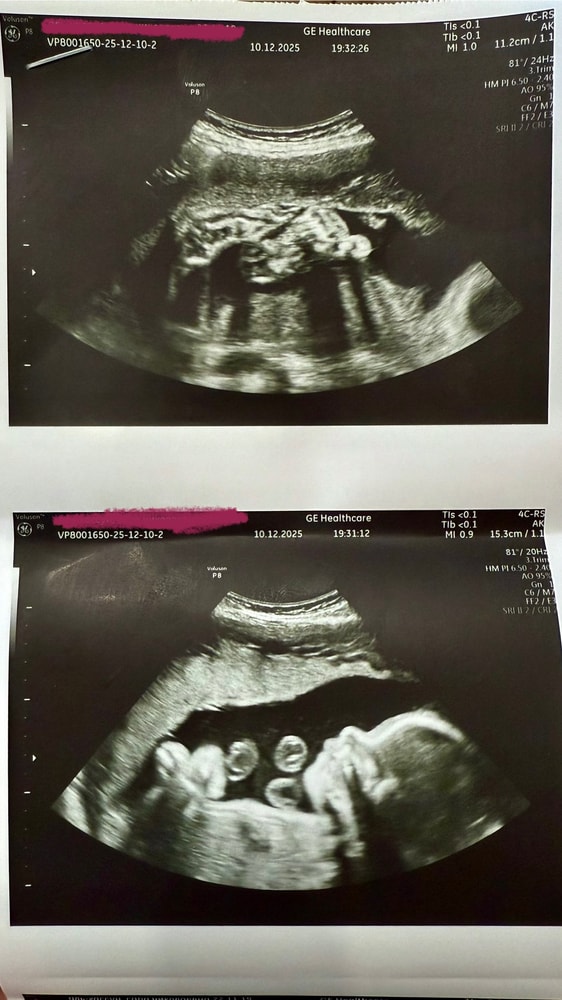

Наши будни, наши неделькиБыла на узи сегодня, проверить что происходит- последние 4 дня шевеления малыша стали, во первых, просто очень активными, продолжительными и частыми (почти 50% времени дня), во вторых, стали располагаться вместо боков живота прямо посередине внизу, ощущения у самого «выхода», да еще и больно ужасно. В итоге все с нами обоими в порядке, лежит как и лежал, говорят просто ручкой бьет туда, никуда сбегать не собирается 😆 показали пятки сладкие 💕

Единственное что отметили- это что он большой очень, на 2+ недели превышает свой срок по измерениям. То есть сегодня 27+4 у меня, а по размерам и весу уже на 30 недель. Развитие всего хорошее. Откормила, блин, викинга 🥲